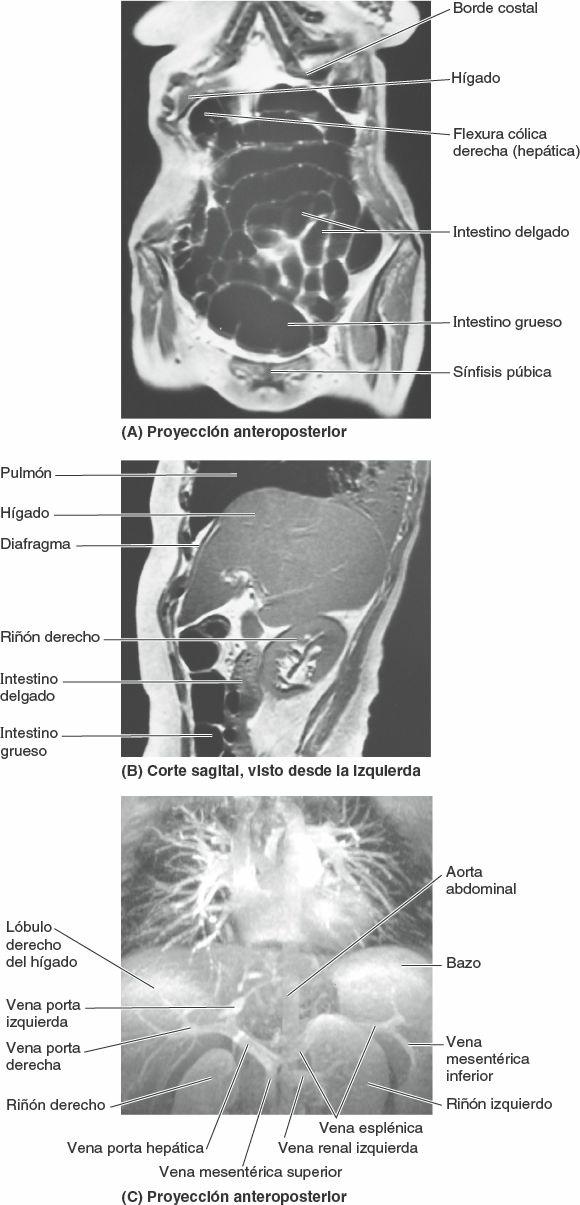

Fig. 5-105. Imágenes por resonancia magnética y angio-RM del abdomen. A) RM coronal a través de las vísceras de la cavidad anterior del abdomen (casi exclusivamente intestinos). B) RM sagital por la línea

medioclavicular derecha. C) Angio-RM anteroposterior que muestra los grandes vasos del tórax, y la aorta y la vena porta hepática en el abdomen.